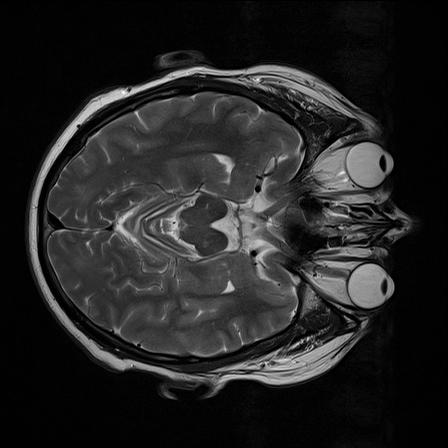

Ich arbeite an der Extraktion der Augen aus MR-Bildern (3D Daten) um im folgenden spezifische Paramter zu bestimmen (Groesse, Volumen...) und sie letztendlich als 3D Modell darzustellen. Leider ergeben sich oftmals durch den schwachen Kontrast zwischen dem Auge und dem umliegenden Gewebe Probleme das Auge korrekt zu extrahieren (z.B. mittels 'region growing').

Leider wird allerding in der Regel wird keine geschlossene Kontur (um das Auge) erkannt, was bei dem folgendem 'region growing algorithmus' dazu fuehrt, dass er ueber das Auge hinaus geht. Zu besseren Vorstellung habe ich ein Originalbild und das Bild nach der Kantendetektion mit angehangen.

nii_eye.jpg |